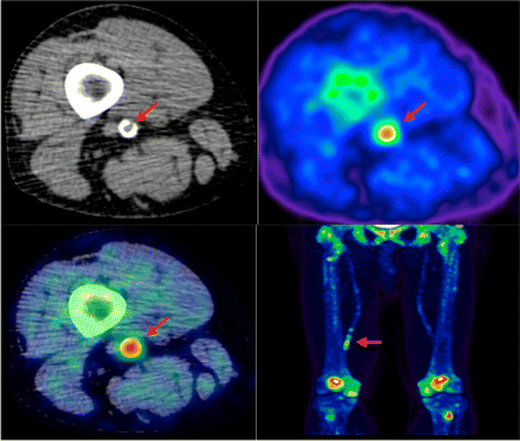

18F-sodium fluoride (NaF) used in PET imaging is able to identify areas of microcalcification in vivo because the radiolabeled fluoride is taken up at sites of mineralization, where it replaces the hydroxyl group of hydroxylapatite [73] (Fig. 3). Work by Irkle et al. validated clinical NaF-PET using NaF against electron microscopy, autoradiography, and microPET for detecting microcalcification in symptomatic carotid endarterectomy histological specimens. Fluoride was shown to co-localize closely and preferentially bind to pathological mineralization, and the increased surface area of microcalcification relative to macrocalcification resulted in increased tracer uptake [74••].

Fig. 3

Lower limb 18F-NaF imaging: non-contrast CT (top left) with a rim of calcification of the vessel, 18F-NaF PET (top right), and fused 18F-NaF PET/CT (bottom left) of the superficial femoral artery (arrow) at the level of the adductor canal, demonstrating significant vessel uptake in this symptomatic patient. In addition, there is prominent uptake seen in the vessel at the same level on the coronal image (bottom right)